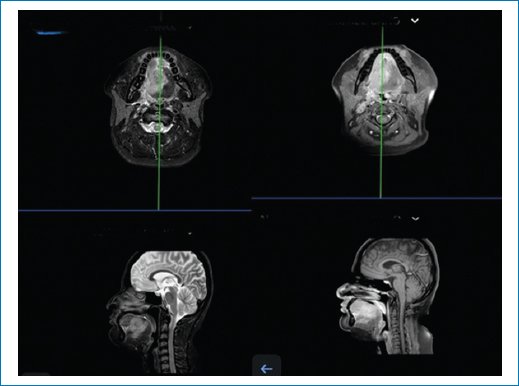

A tongue magnetic resonance imaging (Fig. 1) reported an infiltrative lesion is identified in the posterior two-thirds of the tongue, with irregular, poorly defined borders, predominantly involving the right half and crossing the midline. The lesion measures 42 × 32 × 43 mm in anteroposterior, transverse, and craniocaudal dimensions, respectively. No invasion of adjacent bone is observed.

Figure 1. Pre-operative magnetic resonance imaging of the head and neck. Axial (top row) and sagittal (bottom row) T2-weighted images demonstrate an infiltrative lesion occupying the posterior two-thirds of the tongue, crossing the midline, and displacing adjacent oropharyngeal structures.

Ipsilateral lymphadenopathy is noted in level Ib (12 mm) and level IIa (14 mm) on the right side, both without central necrosis. Additional smaller lymph nodes with well-defined borders and homogeneous enhancement are present in levels Ib, IIa, IIb, and III.

The parotid and submandibular glands appear unremarkable. No abnormalities are observed in the nasopharynx, oropharynx, laryngeal structures, trachea, or cervical esophagus.

Diagnostic impression: infiltrative neoplasm involving the tongue and floor of mouth, associated with secondary nodal involvement, highly suggestive of squamous cell carcinoma.